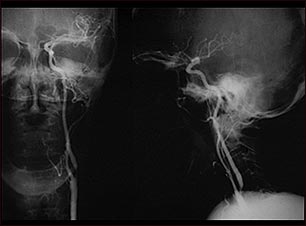

Estenosis carotídea; radiografía de la arteria izquierda

El arteriograma carotídeo es un estudio de rayos X que sirve para determinar si existe una estrechez u otra anomalía en la arteria carótida, que es la arteria principal que va al cerebro. Este es un angiograma de la arteria carótida común izquierda (vista lateral, frontal y anterior) que muestra una estrechez severa (estenosis) de la arteria carótida interna justo más allá de la división de la arteria carótida común hacia las ramas internas y externas.